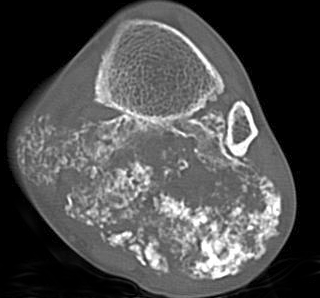

▌膨胀性破坏

膨胀性破坏是地图样破坏的特殊形式,影像学表现为骨质破坏区骨膨胀,周围可见不同程度扩张的骨壳(图 5、图 6、图 7、图 8)。膨胀性破坏是由于肿瘤从骨皮质内面破坏,骨外膜增生形成新生骨造成膨胀的。引起膨胀性破坏见于大多数良性肿瘤和肿瘤样病变如单纯性骨囊肿,动脉瘤样骨囊肿、内生软骨瘤和软骨粘液纤维瘤等,少数也可见于恶性肿瘤如转移瘤、骨髓瘤等。

图 6.膨胀性破坏:骨巨细胞瘤